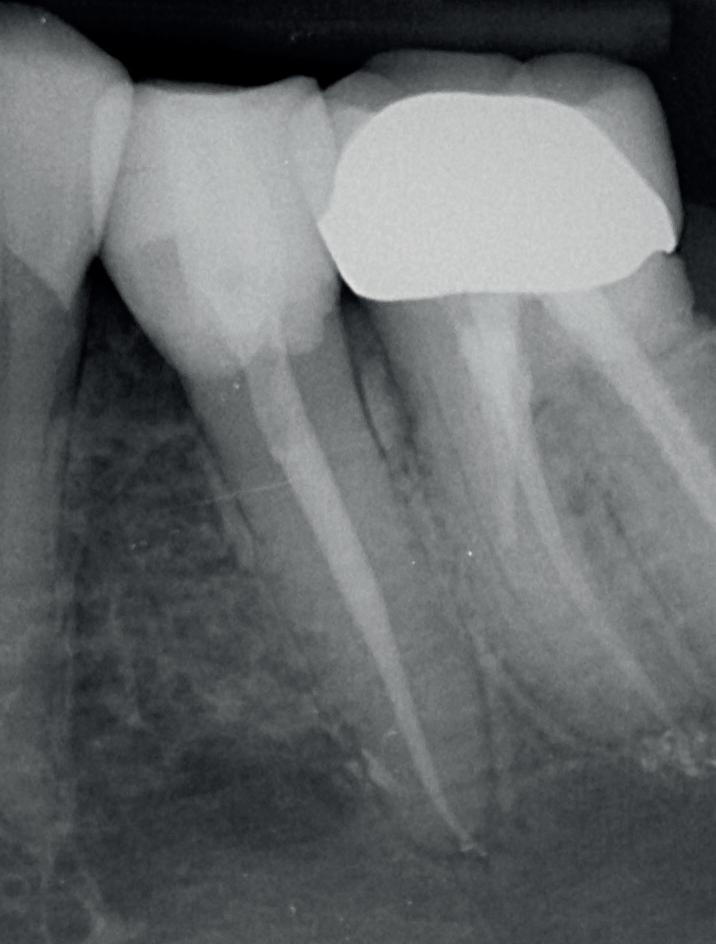

Voordat je aan een wortelkanaalbehandeling begint, zorg je voor (of maak je) een goede beginfoto waar het te behandelen gebitselement volledig op staat afgebeeld. Deze foto geeft essentiële informatie: de grootte van de pulpakamer en de ligging ervan; het aantal en de vorm van de wortels en de breedte van hun wortelkanalen en de lengte van de wortels. Hiermee kan je de DETI-score bepalen en de moeilijkheidsgraad inschatten. De grootte en de ligging van de pulpakamer op de röntgenfoto in combinatie met de ideale anatomische vorm, zoals in foto 1 is aangegeven, bepaalt de uiteindelijke vormgeving van de opening. Bij de molaren liggen de kanaalingangen in de buurt van de knobbeltoppen. Als die niet meer in originele staat

(kroon, restauratie) zijn, kan je ook de wortel gebruiken. Soms moet je net subgingivaal sonderen, maar de kanaalingang ligt in het middel van de wortel. Als je die plek visualiseert en projecteert op je opening, boor je de goede kant op. Nog een tip: wees bij het openen niet spaarzaam met het wegnemen van aanwezig restauratiemateriaal (wees wél spaarzaam met het onnodig wegnemen van tandweefsel).

1. De locatie van de kanaalingangen ten opzichte van de occlusale morfologie (rood). In zwart is de ideale of standaard opening ingetekend. De uiteindelijke vorm van de opening is voorts ook afhankelijk van de klinische situatie, die vooral vanuit een goede begin foto wordt verkregen.

2. Het afgebroken instrument op de foto van de verwijzend tandarts.

3. De opening is vrij klein gekozen. In rood is de ideale opening aangegeven, de tandarts had veel meer restauratiemateriaal mogen wegnemen.